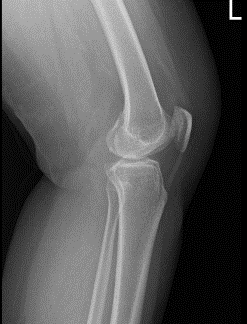

A 66-year-old patient was in our office with complaints regarding left knee pain. She has been experiencing this pain for a month. She denies any injury to the knee. She went to her PCP who recommended x ray showing bone on bone. She presented an Xray result that showed no significant degenerative changes.

There are no acute fractures. She also presented an MRI results that showed trace joint effusion. Tiny popliteal cyst. Minimal lateral patellar shift. Degenerative medial and lateral meniscus tears as detailed above. Minimal osteoarthritis in the medial and lateral joint compartment of the left knee.

Left Knee X-ray AP and Lateral with Oblique 3 views